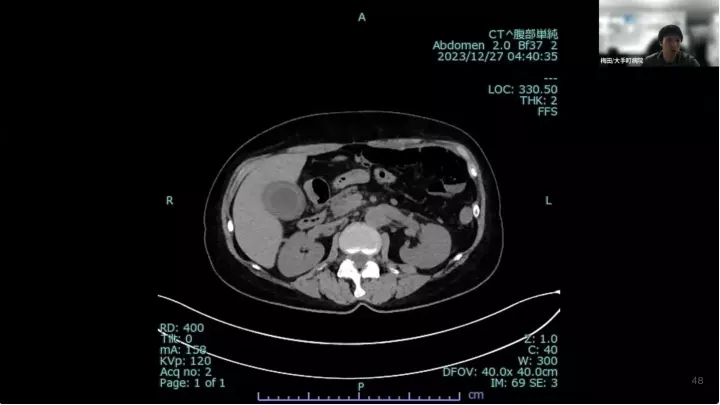

外科医目線の~急性胆嚢炎~治療編